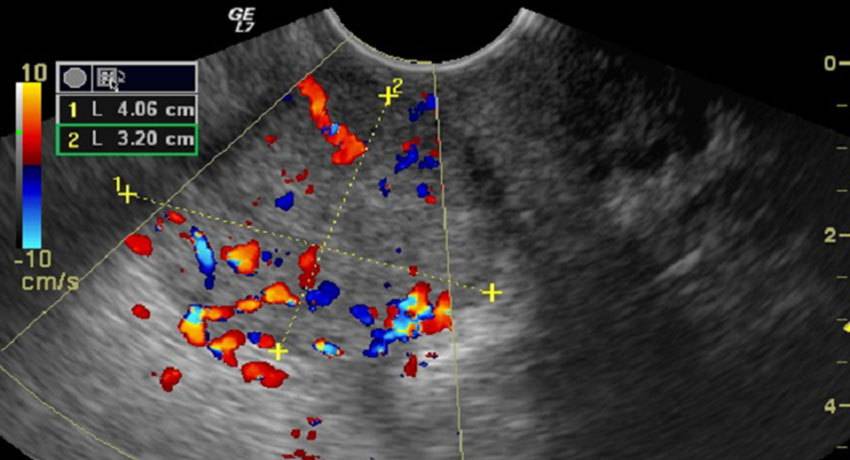

Орган расположен выше верхней тазовой плоскости. Причинами служат спайки, опухоли прямой кишки, яичника (как на фотографии).